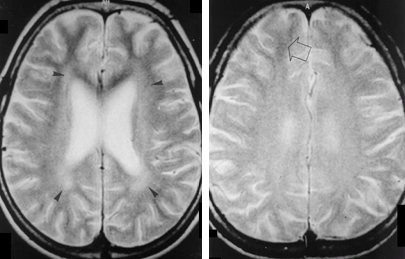

慢性有機溶剤依存患者のMRI T2強調画像

img

1: 福居顯二先生ご提供